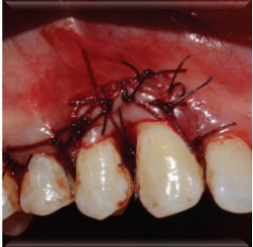

计划切除增生牙龈。由于增生范围较大,拟利用腭侧牙龈进行软组织修复。